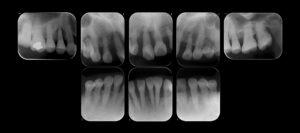

デンタルレントゲン写真と歯周組織検査の結果から、重度の歯周炎に罹患しており(広汎型 重度慢性歯周炎 ステージⅣグレードC)していました。口腔清掃不良による歯周炎の進行と、下顎両側大臼歯の欠損放置に伴って前歯部に噛み合わせの力が強くかかり(二次性の咬合性外傷)、歯槽骨吸収が進行するとともに上下顎ともに歯の病的な位置異常が生じたと考えます.主訴である上顎右側中切歯は、抜歯が適当と考えました。

歯列矯正処置の後、最終的な歯の修復処置(ダイレクトボンディング)を行い、メインテナンスへ移行しました.早期に製作した部分入れ歯は今後も使用していきます。初診時と比較して、歯肉の炎症を認めず、出血点はほぼ消失し、歯の周りの歯槽骨梁の改善が認められました。